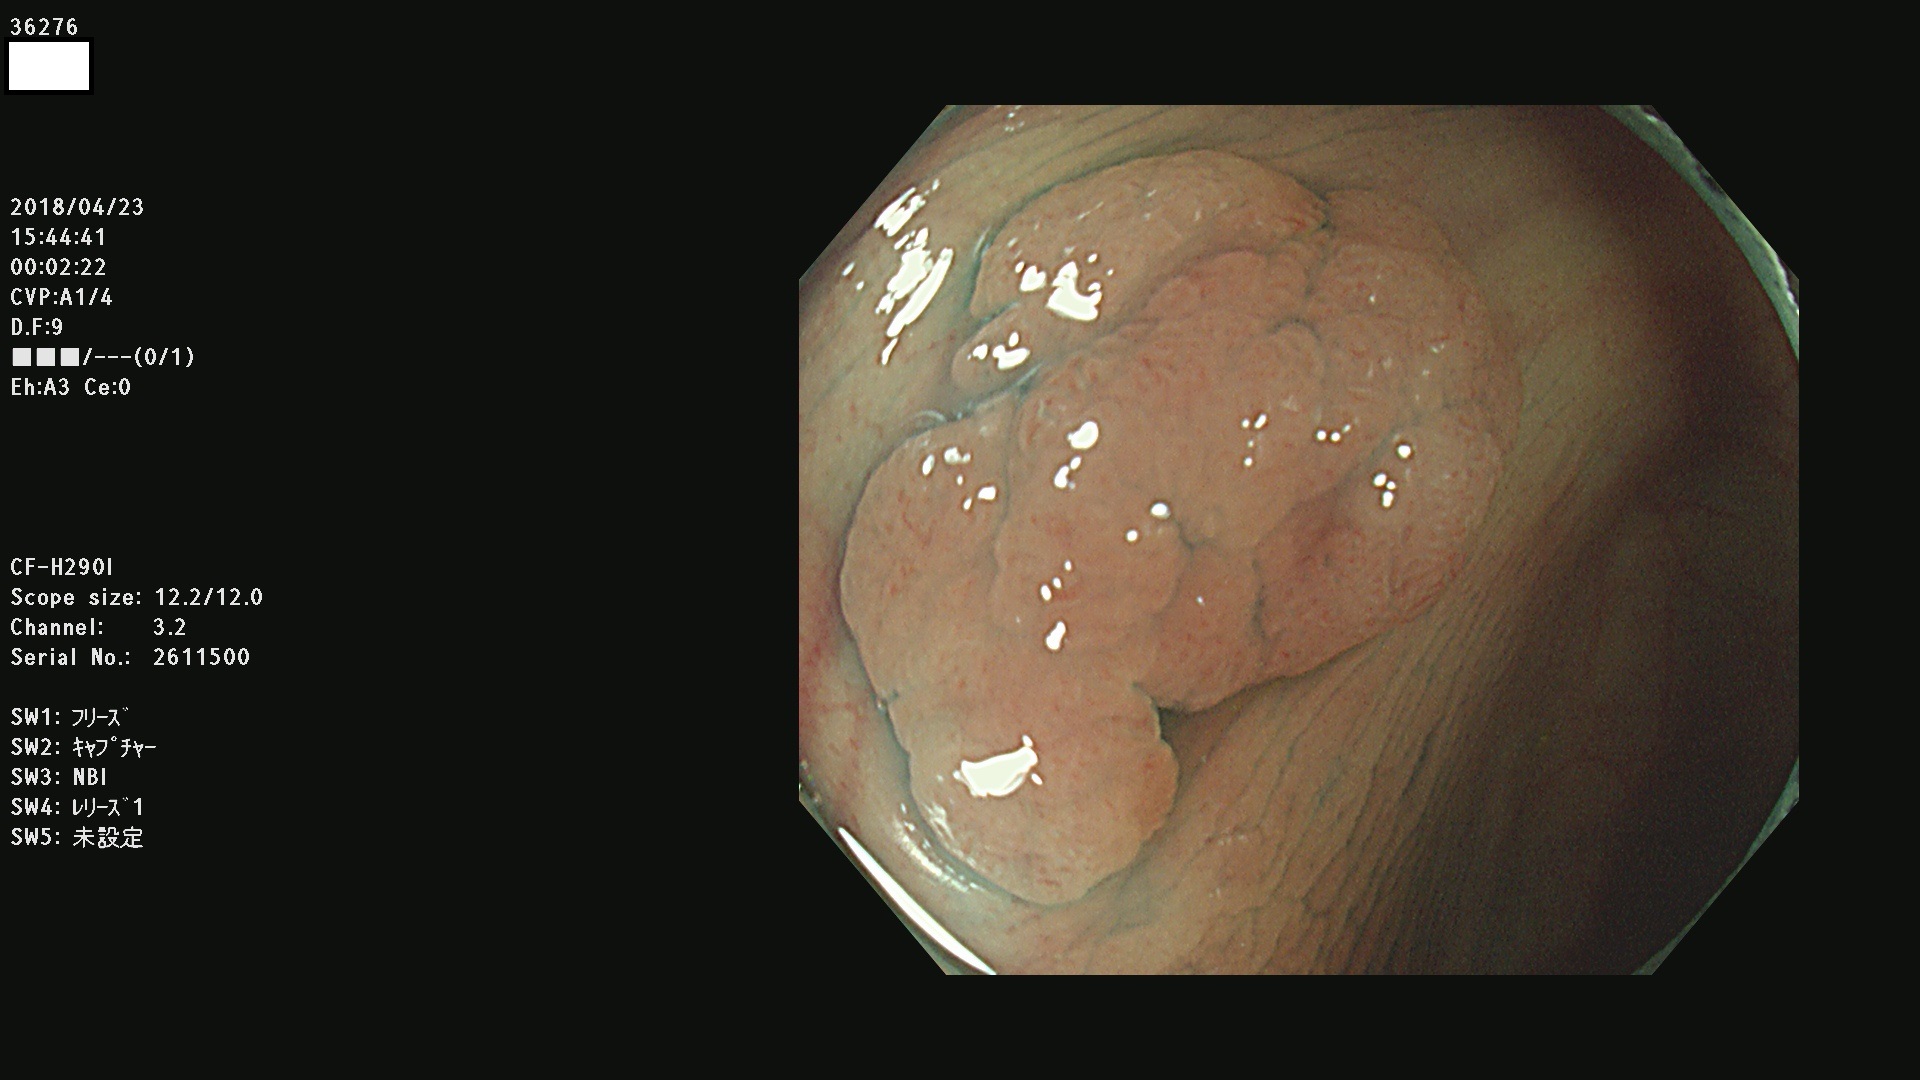

36201 36202 36203 36205 36207 36209 36210 36212 36213 36214 36215 36217 36220 36221 36222 36224 36225 36226 36227 36229 36230 36231 36232 36235 36236 36238 36240 36243 36244 36246 36247(SSAPのみ。SPS) 36248 36249 36251 36252 36253 36254 36255 36256 36257 36258 36259 36261 36262 36264 36265 36267 36269 36270 36272 36274 36275 36276 36279 36280 36281 36283 36285 36288 36289 36291 36292 36295 36296 36297 36299

発見困難で危険性の高い平坦型病変(上記100名より抽出)